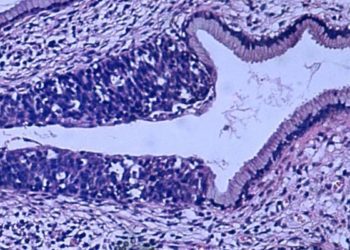

Image: CC/Wiki